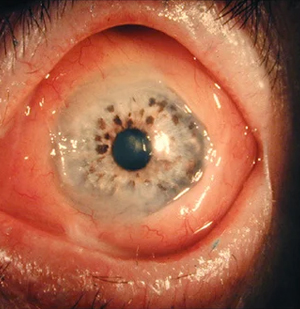

Dr. Tekchandani specializes in a wide range of eye conditions including retinal and vitreous diseases, diabetic retinopathy, macular degeneration, retinal detachment, cataract, glaucoma, refractive errors, and retinopathy of prematurity. He also has expertise in ocular oncology and neuro-ophthalmology.

Vitreoretinal surgery is a highly specialized field of ophthalmology dealing with diseases of the retina and vitreous — the innermost structures of the eye responsible for vision. Dr. Tekchandani performs advanced procedures such as pars plana vitrectomy, scleral buckling, and macular hole surgery to restore and preserve sight.

Retinopathy of Prematurity is a condition affecting premature babies, leading to abnormal blood vessel growth in the retina. Dr. Tekchandani offers comprehensive ROP management, including laser photocoagulation, intravitreal injections, and surgical treatment for advanced stages.